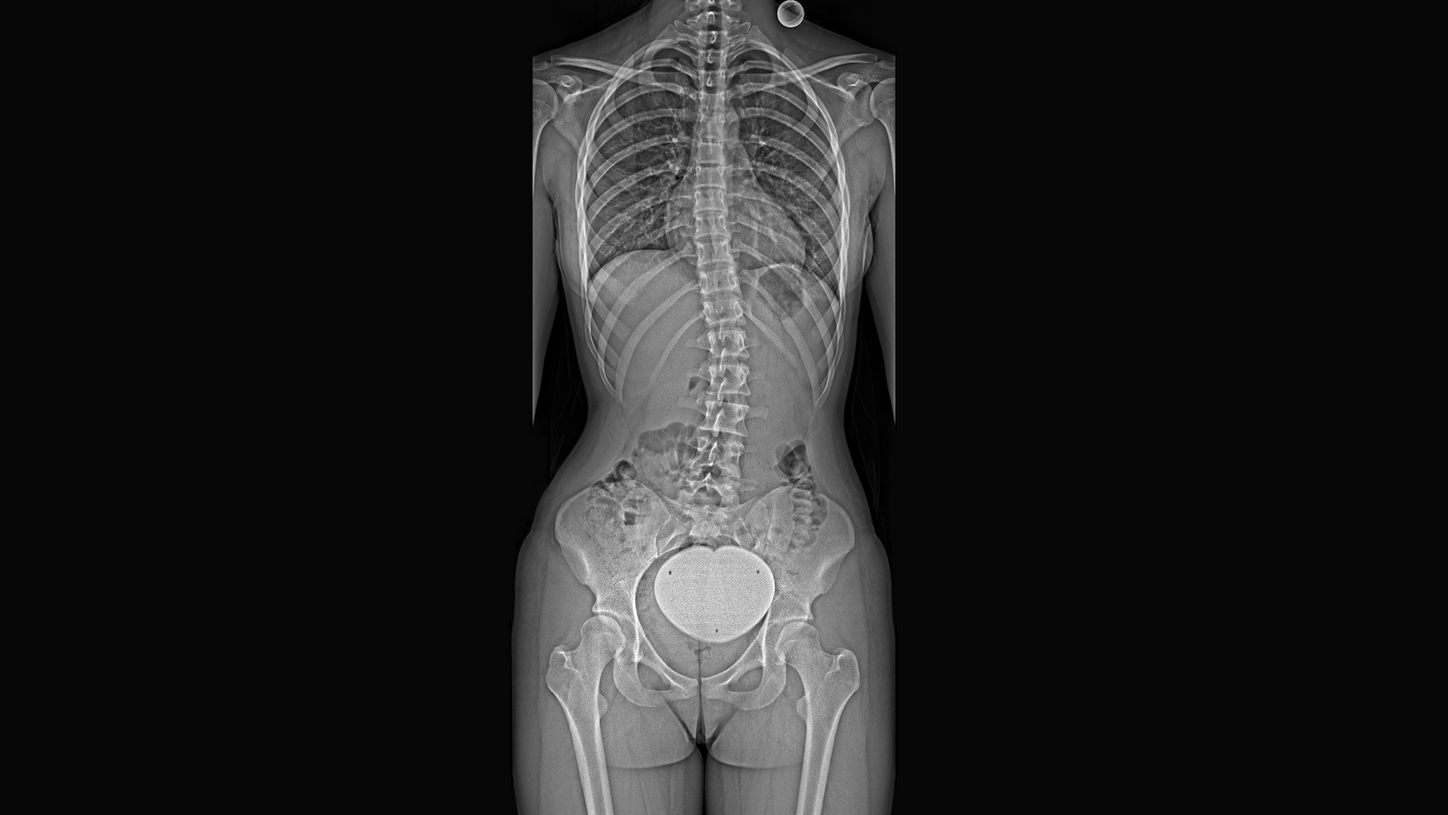

A flexible, holistic spine surgery solution Multitom Rax and Medtronic: A seamless partnership

Spine surgery demands accuracy, efficiency, and confidence. That’s why we’re partnering with Medtronic, which has decades of leadership in spine care. Together, we offer spine surgeons a comprehensive, integrated solution that meets modern surgical needs.